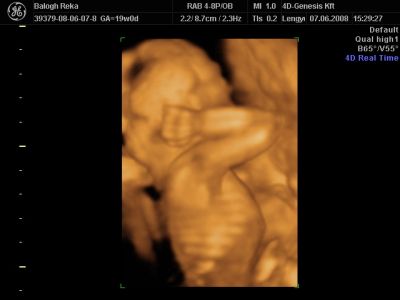

Huhh, hát annyira jó élmény volt, most tök boldog vagyok! Nagyon örülök, hogy mégis elmentem mégegyszer, mert sokat vacilláltam ám. A 4D Genesis egyszerűen szuper, mindenkinek nagyon nagyon tudom ajánlani, ezen belül is engem a Lengyel Györgyné Márti fogadott. Szuper ez a nő, akkora átéléssel és profizmussal csinálta az egész vizsgálatot! Mindent részletesen megnézett, megmutatott, elmagyarázott, nem sajnálta az időt. A felvétel gyönyörű lett, az egész baby nagyon szépen látszik, végig fent volt és mocorgott, hihetetlen aranyos volt, és nagyon szép!

Bemutatott párszor, ezek mind meg is vannak örökítve!

Na és a lényeg...jöjjenek a sztárfotók! Bocsi előre, 8 lesz és kicsit nagyok, de nem tudtam választani, azokat a bemutatásokat mind muszáj volt felraknom, tök vicces!